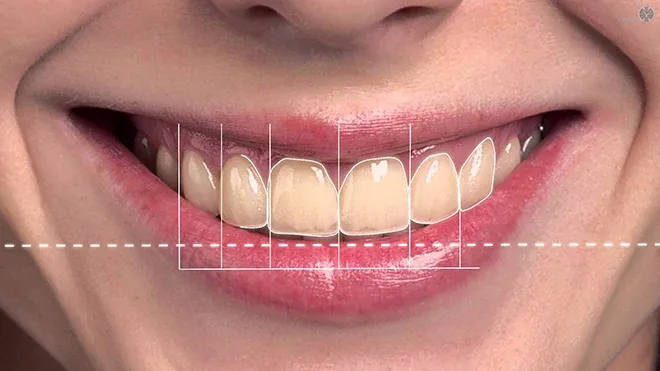

Một nụ cười được xem là hài hòa và thẩm mỹ cần đáp ứng các tiêu chí “chuẩn tỷ lệ vàng” được ứng dụng rộng rãi trong nha khoa thẩm mỹ hiện đại. Trước hết, đường cười (Smile Arc) phải chuẩn: viền răng cửa hàm trên cần song song với đường cong của môi dưới khi cười, tạo nên tổng thể mềm mại và tự nhiên. Tỷ lệ Răng – Nướu – Môi cũng giữ vai trò quan trọng, trong đó phần nướu lộ ra khi cười không vượt quá 2mm, và răng đạt tỷ lệ chiều cao – chiều rộng lý tưởng khoảng 80%. Về màu sắc và hình dáng, răng phải trắng sáng vừa phải, có độ trong tự nhiên, đồng thời dáng răng cần phù hợp với hình thái khuôn mặt — răng dáng tròn cho khuôn mặt tròn, dáng vuông cho khuôn mặt góc cạnh. Bên cạnh đó, khớp cắn chuẩn giúp hai hàm khít sát, không hô móm, đảm bảo cả thẩm mỹ, phát âm và chức năng ăn nhai.

Tại Nha khoa Dr. Green, các bác sĩ luôn dựa trên những tiêu chí khoa học này, kết hợp với công nghệ thiết kế nụ cười DSD (Digital Smile Design) để đảm bảo mỗi nụ cười được kiến tạo đều là độc bản và hoàn hảo nhất.